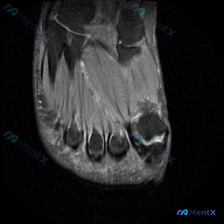

给大家分享一份足部MRI读片病例,整理了完整的分析思路,一起来讨论一下。 病例影像基本信息 这是一份足部前足区域(跖骨头/趾骨近端水平)的横断面MRI T2序列图像,核心观察结果如下: 1. 骨骼:中央跖骨头/趾骨骨皮质呈低信号,骨髓腔信号正常 2. 软组织:骨骼周围可见广泛不均匀信号异常,T2序列...